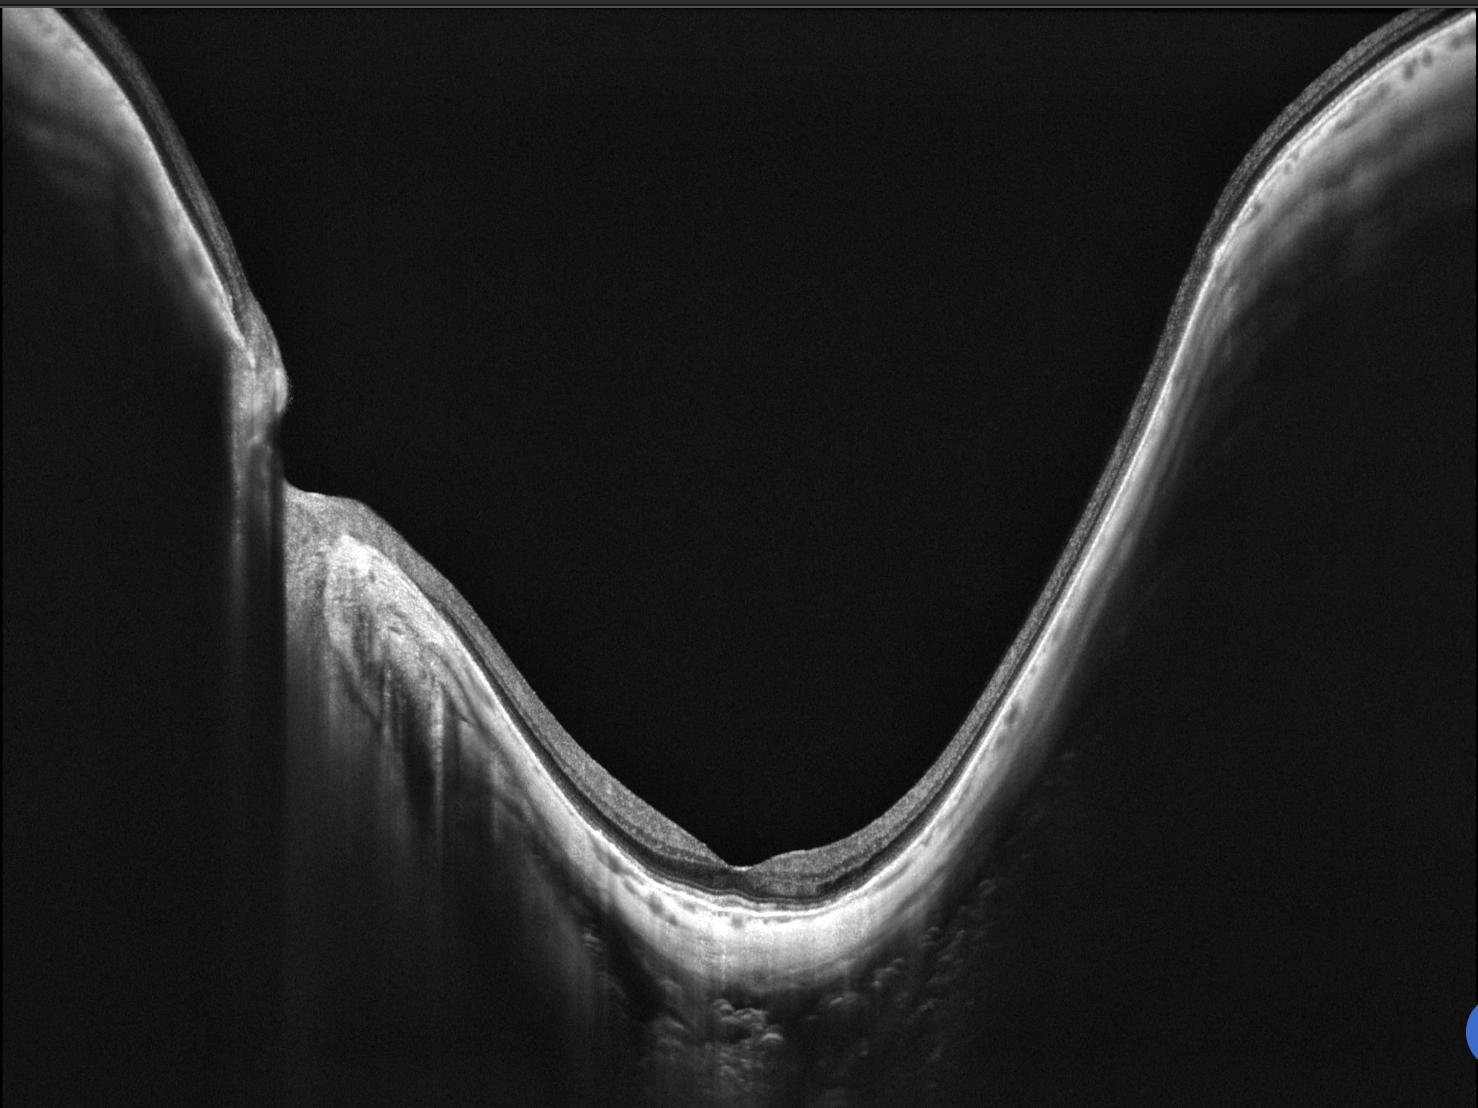

OCT Intalight montrant un staphylome myopique fovéolaire

OCT Intalight — Staphylome myopique fovéolaire (IPO Paris)